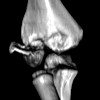

Рентгенография мягких тканей туловища

Рентгенография мягких тканей организма. Рентгенологическое исследование мягких тканей (кожи, подкожного жира, мышц, связок, сухожилий ). Окружает грудную клетку и формирует брюшную полость. Это позволяет оценить внутреннюю структуру и целостность различных структур мягких тканей, определить образование масс различной природы, инфекционно-воспалительные процессы и травматические повреждения мягких тканей. Этот метод чаще используется как часть мониторинга больницы, реже используется в амбулаторных условиях. Первоначальная подготовка требуется для планового лечения и может включать специальную диету, если необходимо обследование мягких тканей брюшной полости и забрюшинного пространства. В некоторых случаях используется контрастное вещество.